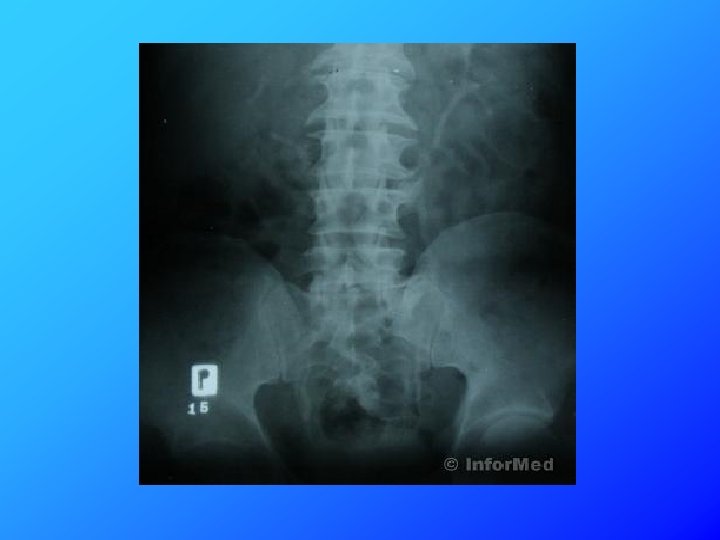

Do lekarza rodzinnego zgłosiła się 55 -letnia pacjentka z bólem w okolicach odcinka L-S kręgosłupa. Bóle pojawiły się 4 miesiące temu, początkowo występowały głównie po wysiłku fizycznym lub po przeciążeniu, od około 2 miesięcy występują również w spoczynku. Z odchyleń w badaniu przedmiotowym stwierdzono tylko niewielka bolesność w okolicy L 4. Pacjentka zgłosiła się z badaniami dodatkowymi zleconymi przez innego lekarza. RTG odc. L/S – zwężenie przestrzeni międzykręgowej L 5/S 1. Początkowe zmiany zwyrodnieniowe. Delikatne skręcenie w lewo.

U pacjenta rozpoznano zesztywniające zapalenie stawów kręgosłupa (ZZSK), które powoduje zarastanie przestrzeni międzykręgowych. Zmiany ograniczają ruchomość kręgosłupa dając na zdjęciach RTG charakterystyczny obraz „kija bambusowego”.